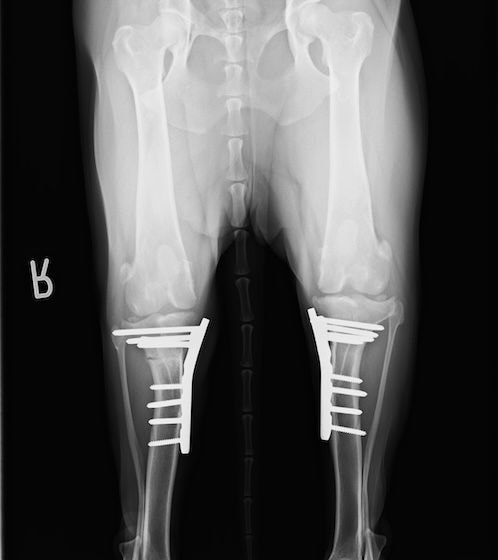

左後肢の挙上を主訴に来院されました。触診にて両関節の前方引き出し兆候、両膝蓋骨の内方脱臼を認めました。関節液検査より免疫介在性多発性関節炎は否定的でした。レントゲン検査にてfat pad signを伴う関節炎が認められたことから、前十字靭帯断裂と膝蓋骨内方脱臼(左GradeⅢ 右GradeⅢ〜IV)併発と診断し、手術を行いました。

手術は片足ずつ行い、両膝とも術中の関節鏡検査にて前十字靭帯の完全断裂と半月板損傷を確認しました。TPLO、半月板切除と滑車溝形成を始めとした膝蓋骨脱臼整復術を実施いたしました。膝蓋骨の安定化を測るために外側支帯を強固に縫合し、内側支帯は切除し縫合せずに開放状態にしています。

術後の歩行状態は良好です。

術前正面像

術後左後肢正面像

術前のTPAは左後肢33.1°右後肢26.8°でしたがTPLO実施により左後肢5.5°右後肢12°に矯正されました。